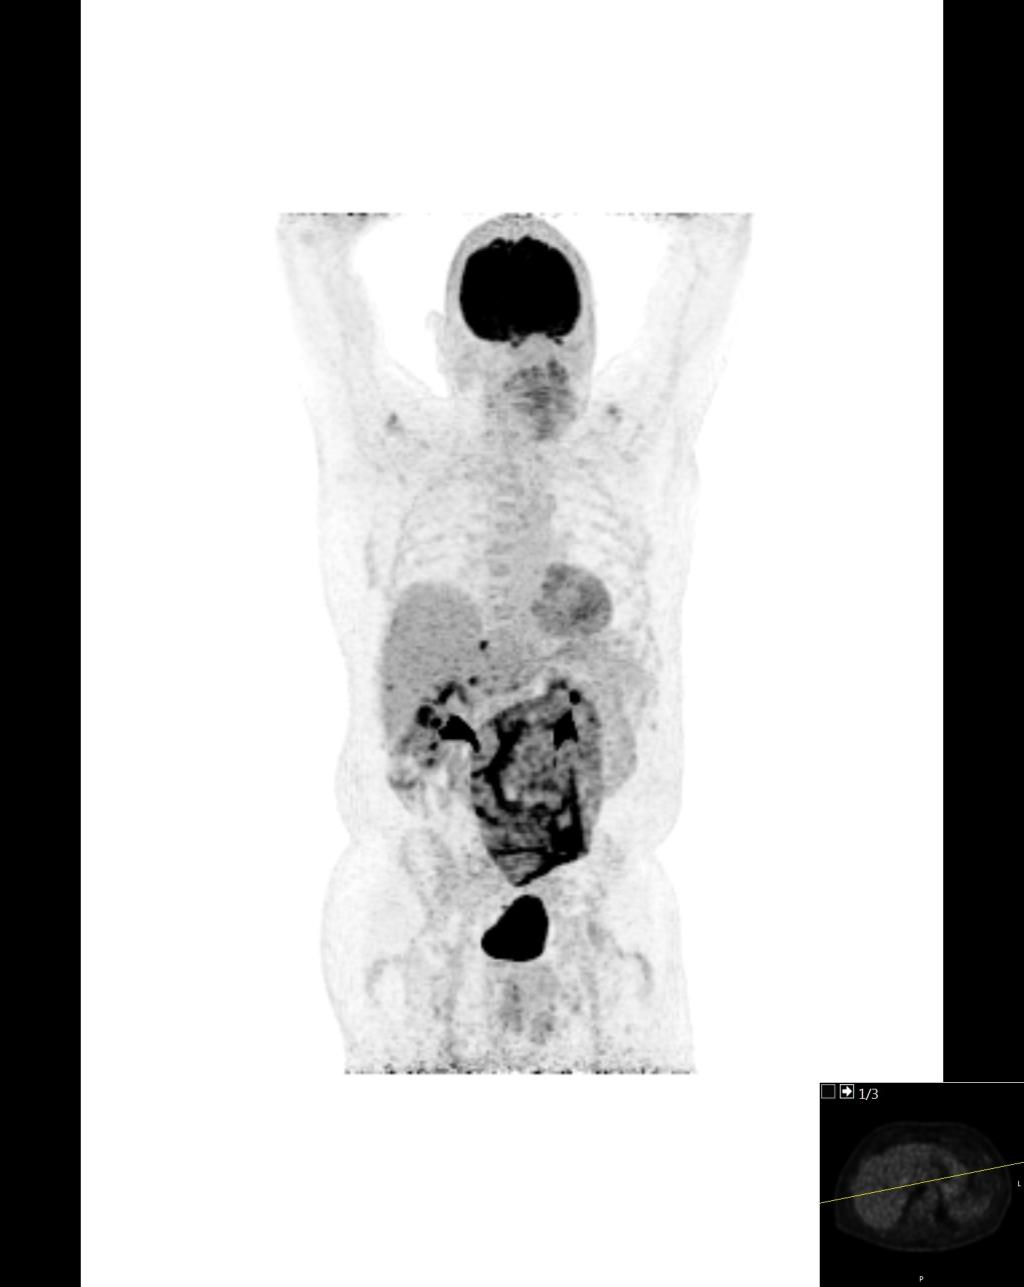

Op een 18FDG-PET-CT-scan van een 65-jarige man met een rectumcarcinoom zijn nodulaire afwijkingen van de buikwand te zien. Patiënt is recent geopereerd aan een navelbreuk, maar hij heeft geen buikpijn en de ontstekingsparameters zijn niet-afwijkend. Op een blanco CT-scan waren de nodulaire afwijkingen niet zichtbaar.